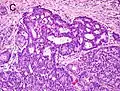

Gleason score 7 (3+4) with minor component of cribriform glands

Gleason score 8 (4+4) with glomeruloid glands

Gleason 4

Gleason pattern 4 glands are no longer single/separated glands like those seen in patterns 1-3. They look fused together, difficult to distinguish, with rare lumen formation vs Gleason 1-3 which usually all have open lumens (spaces) within the glands, or can be cribriform-(resembling the cribriform plate/similar to a sieve: an item with many perforations). Fused glands are chains, nests, or groups of glands that are no longer entirely separated by stroma-(connective tissue that normally separates individual glands in this case). Fused glands contain occasional stroma giving the appearance of "partial" separation of the glands. Due to this partial separation, fused glands sometimes have a scalloped (think looking at a slice of bread with bite taken out of it) appearance at their edges.[4][7]